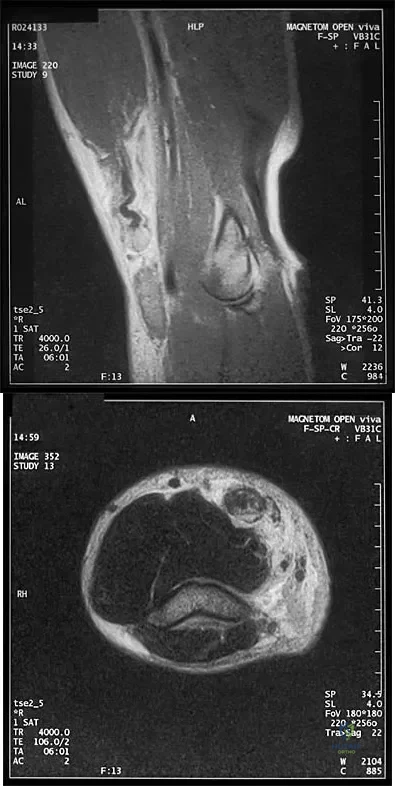

Question 99

A 32-year-old powerlifter who was performing a dead lift 3 days ago noted a sharp pain in the front of his dominant right arm just after beginning to lower the weight. He now reports pain in the anterior aspect of the arm that worsens when he opens a door. Examination reveals moderate ecchymosis and swelling of the forearm and tenderness in the antecubital fossa. The MRI scans are shown in Figures 15a and 15b. If the injury is left unrepaired, the greatest functional deficit will most likely be the loss of

Explanation